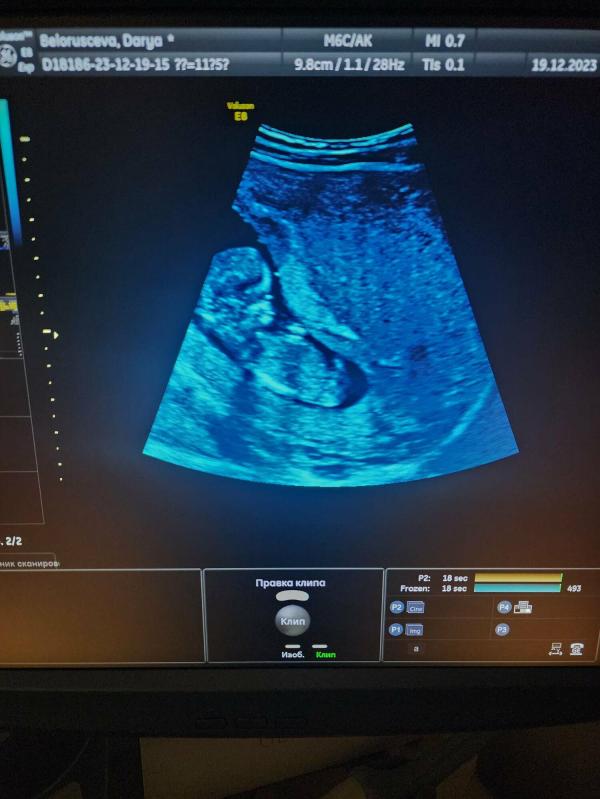

Девчонки, как думаете: М или Д, что лучше? Ваши мнения, советы и опыт!

Девчули, как думаете М или Д ?

Если это внизу не ноги, а половой бугорок, то мальчик, а если ноги, то не видать😁

27.12.2023 Нравится Ответить

Вот тоже думаю, по форме черепа и если это не ноги то парень)